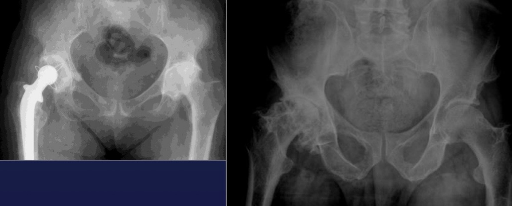

Hip

Coxarthrosis

Arthrosis Rx

GENERAL Rx signs

Joint space narrowing (even or uneven)

Subchondral OS

Subchondral cysts

Osteophytes

Large proximal joints : hips, shoulder